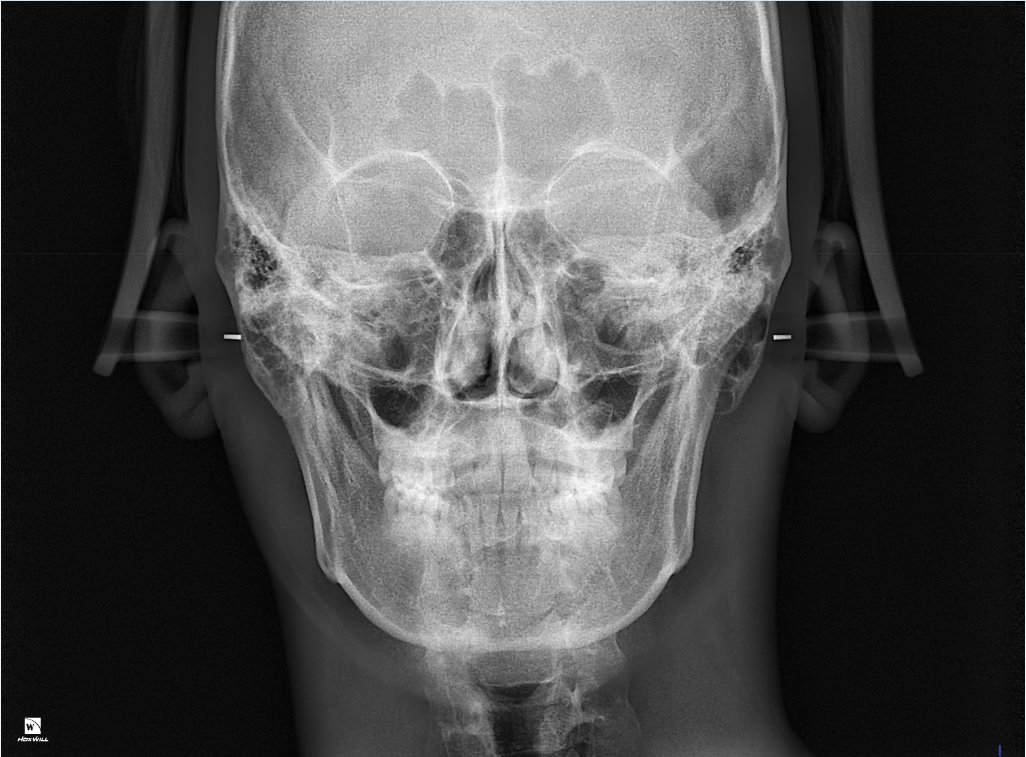

턱 틀어짐을 평가할 때는 턱부분만 보지 않습니다. 동공간선과 턱끝 등을 평가하게 됩니다. 골격적으로 보았을 때, 틀어짐이 나타나고 있기는 하나 이것이 정상범주에서 크게 벗어나지 않으며 대부분 이정도의 canting은 본인이 크게 심미적으로 문제가 되지 않는다고 판단된다면 수술이나 교정을 요하는 것은 아닙니다.

엑스레이 사진상으로는 약간 틀어진것으로 보이지만 크게 비대칭은 아닌것으로 보입니다 .